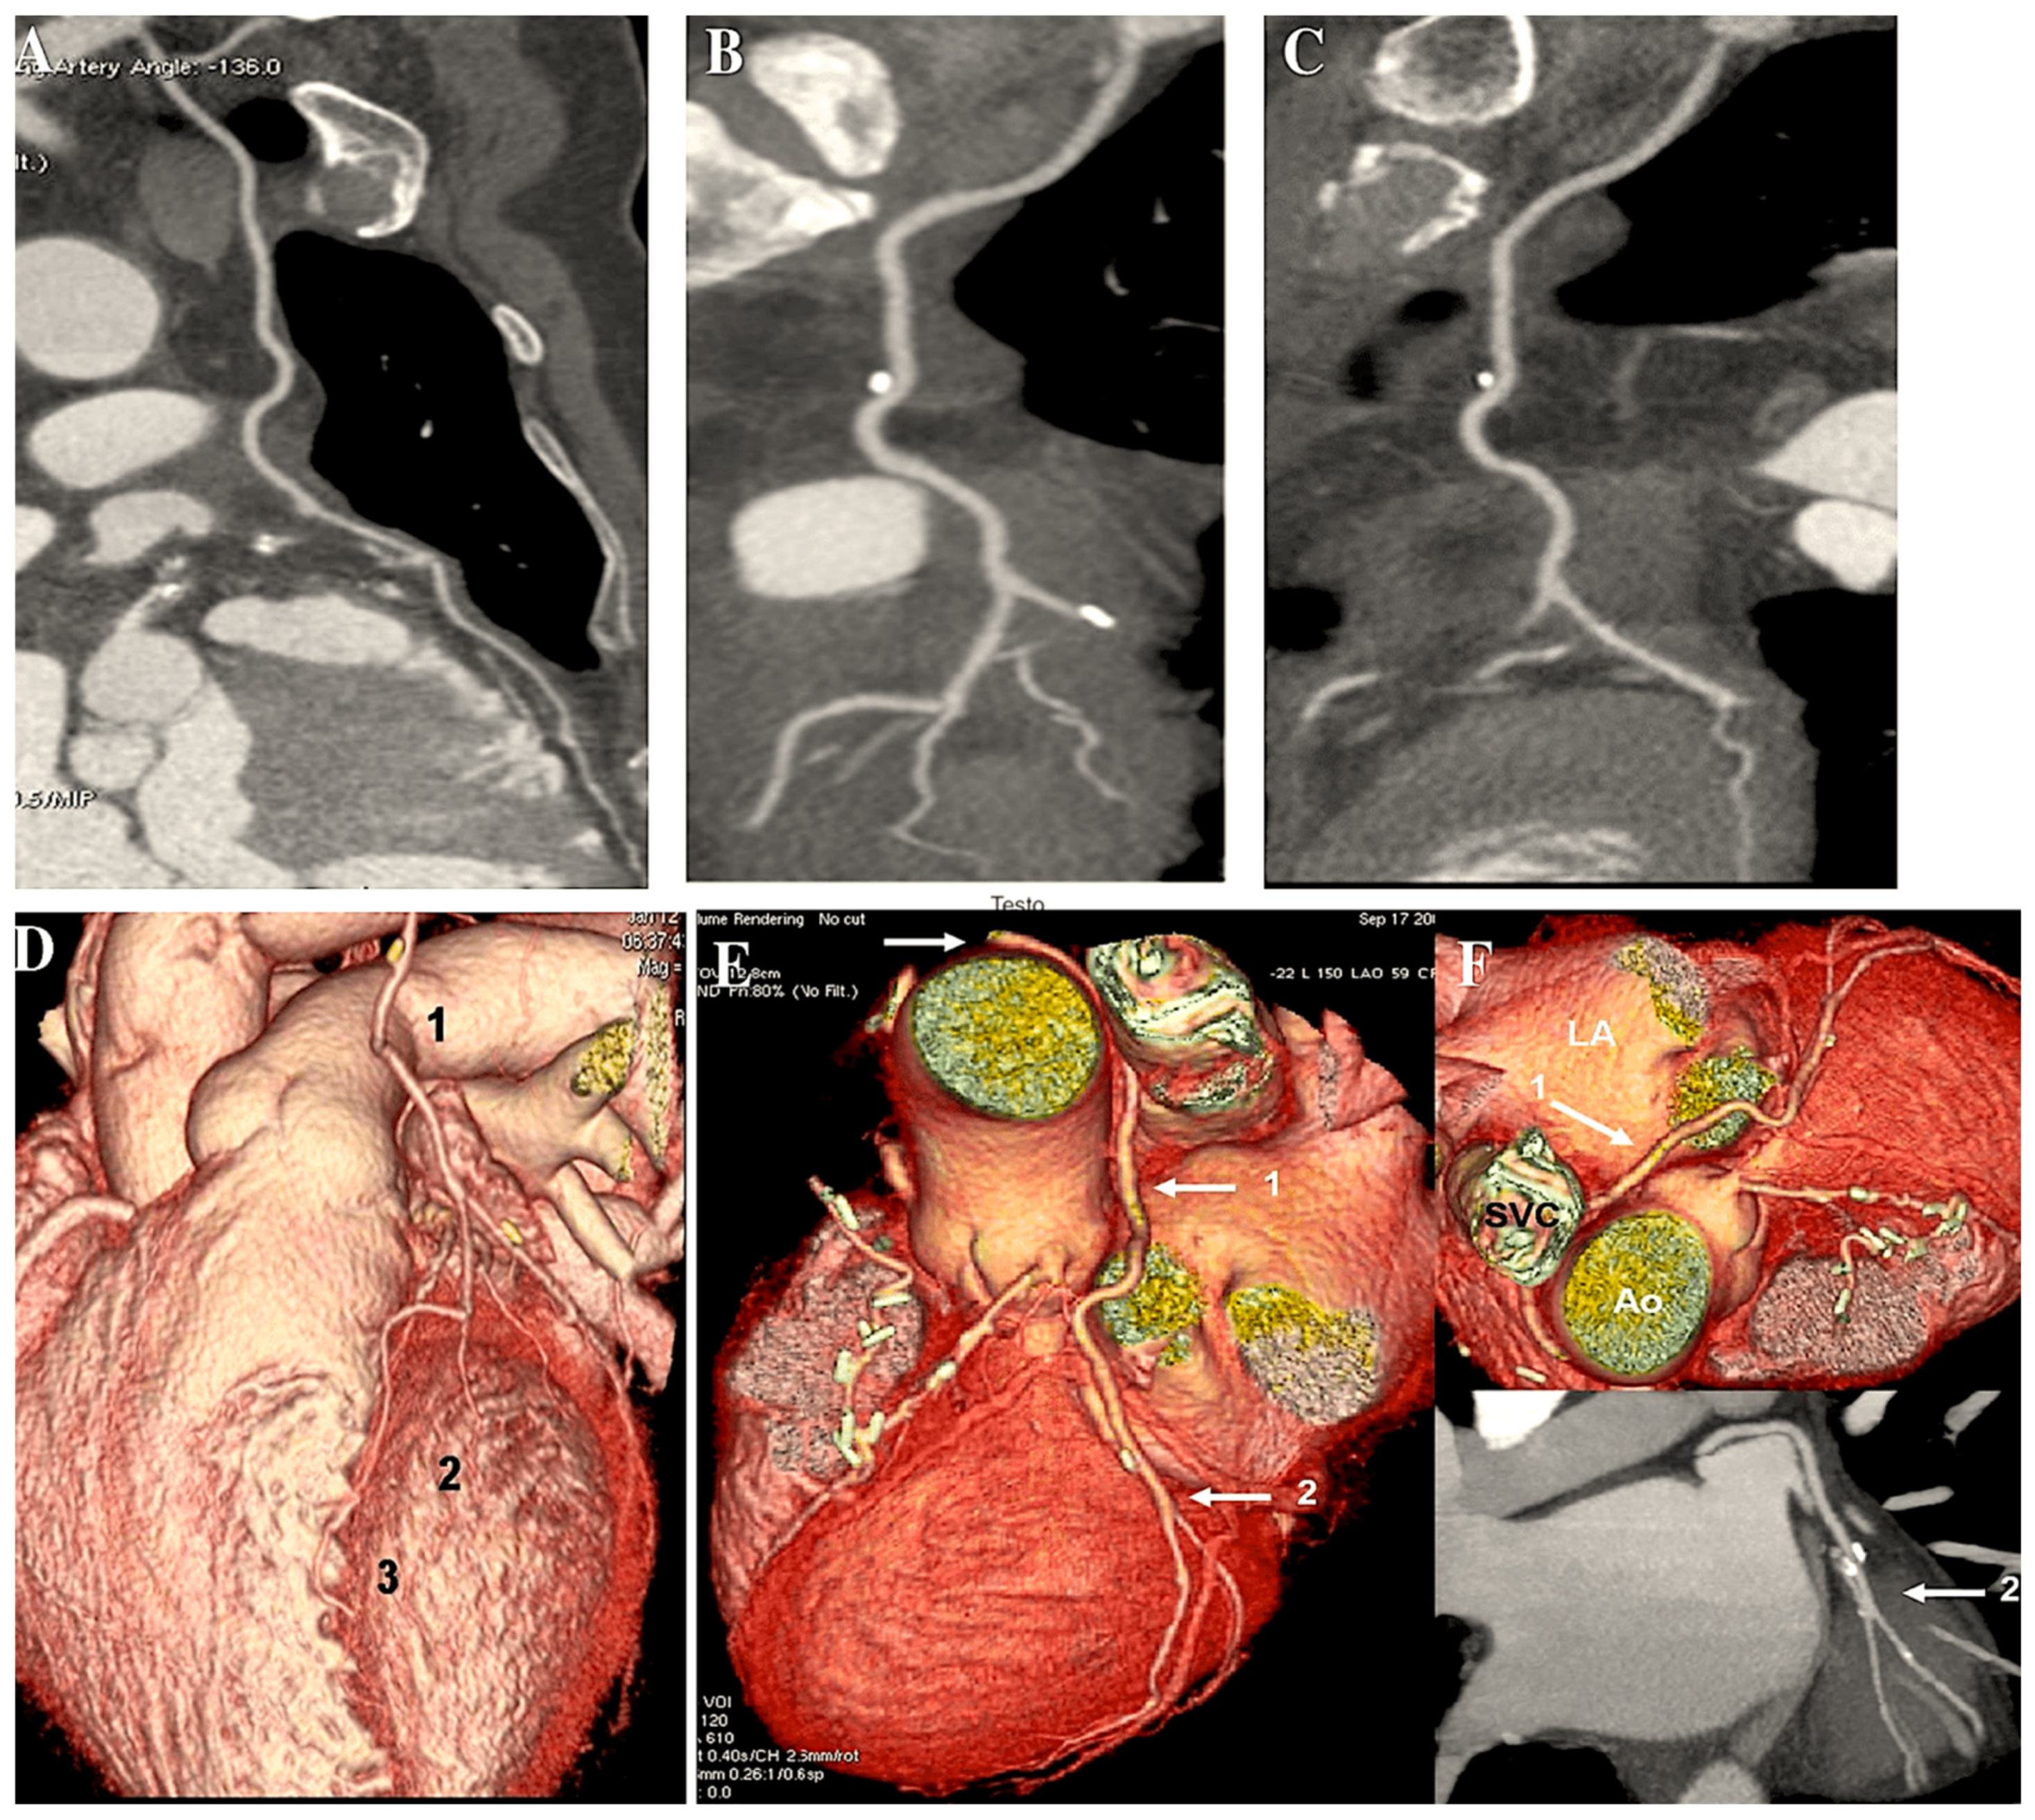

In the case of in situ arterial grafts (such as a left internal thoracic artery graft), the native arterial inflow is retained, thus necessitating an alternative approach (Figure 3).

Figure 3.

The CABG procedure was conducted using arterial conduit (A–C) and including BITA in a Y-shaped configuration (A), the gastroepiploic artery (B), and pedicled LITA-RITA and RA (C). (A): 1. Left internal thoracic artery (LITA); 2. LITA on diagonal branch; 3. LITA on left anterior descending artery (LAD). (B): Gastroepiploic artery on right coronary artery (RCA). (C): 1. Right internal thoracic artery (RITA) on RCA; 2. LITA on LAD; 3. radial artery (RA) on first obtuse branch.

The RA conduit can be employed for sequential revascularisation and sutured as Y-graft to LITA (Figure 4A). Moreover, it is considered to be a prime location for performing proximal anastomosis on an additional RA conduit (Figure 4A). Such conduits may comprise an additional radial artery graft or a free RITA (Figure 4B,C).

Figure 4.

The illustration depicts a CABG procedure utilising bilateral internal thoracic arteries anastomosed with Y-graft technique (A–C). (A): Conventional angiogram demonstrates the patency of the RA. The radial artery is employed as a Y-graft technique (LITA-RA-Y) for sequential anastomoses. (B,C): The Y-graft technique (LITA-RITA-Y) is utilised on the left anterior descending artery (LAD) and on the second marginal branch. 1. LITA-LAD; 2. LITA-RITA-Y; 3. RITA-second marginal branch. Abbreviations: LAD, left anterior descending; LITA, left internal thoracic artery; RA, radial artery; RITA, right internal thoracic artery.